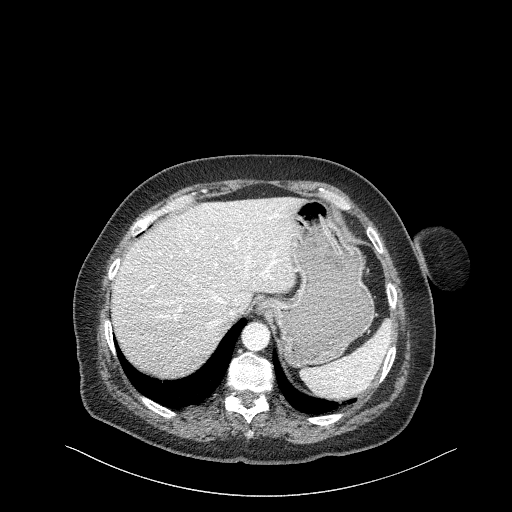

Generated VENOUS CT scan (A→B translation)

Full window (WL 1023.5, WW 4095 β†’ Low βˆ’1024, High +3071)